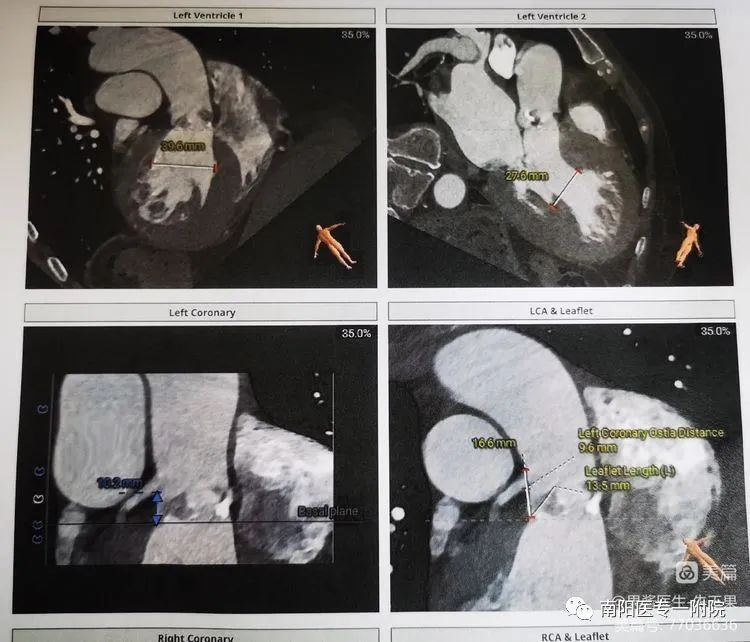

术前评估流程